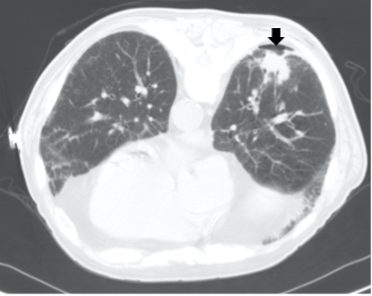

Diagnostic testing. A CT scan performed immediately after the biopsy identified a small pneumothorax that did not require chest tube placement at the biopsy site (Figure 2).

Figure 2. CT scan showing a small loculated pneumothorax (black arrow) at the biopsy site post-procedure.